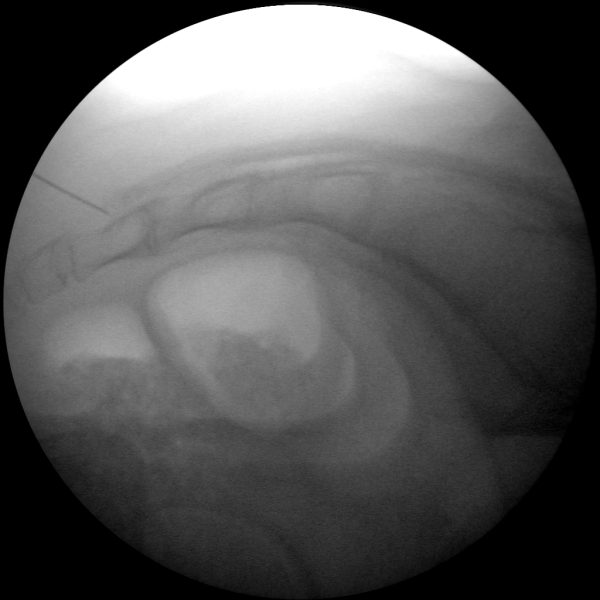

Skan-C proves highly effective in performing joint injections, a procedure commonly used to administer pain-relieving medication directly into the affected joints, such as the knee, shoulder, or hip.

Skan-C is well-suited for performing Spinal Cord Stimulation (SCS), a pain management technique that involves implanting a device to deliver electrical impulses to the spinal cord, altering or blocking pain signals. Skan-C's high-resolution imaging assists pain management professionals in placing the leads precisely and evaluating their position to the spinal cord.